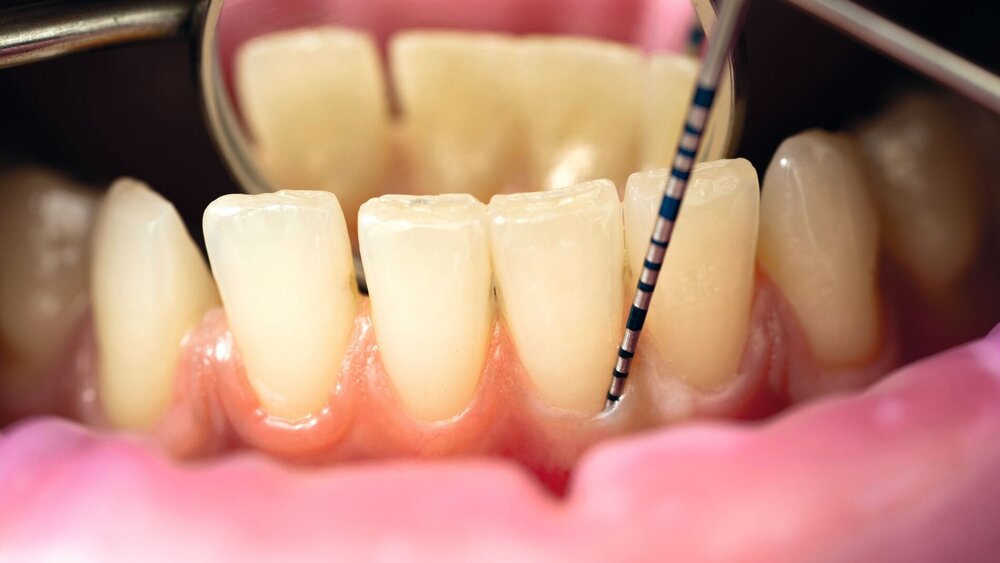

Zunächst wurde vereinbart, dass die Falldefinitionen der Neuen Klassifikation zu parodontaler Gesundheit, Gingivitis und Parodontitis als Referenzstandard in diagnostischen Studien dienen sollen. Von der Arbeitsgruppe 1 wurde die manuelle parodontale Sondierung als „Standard of Care“ bestätigt, da diese gleichzeitig die Erfassung der wichtigsten diagnostischen Parameter Sondierungstiefe, klinisches Attachmentniveau und Blutung auf Sondierung erlaubt. Die Genauigkeit und Reproduzierbarkeit der Messungen dieser Parameter und mögliche Fehlerquellen sind in einer Vielzahl von Studien hinreichend untersucht worden. Auch ist die Methode wenig invasiv und kostengünstig.

Komplementär zur klinischen Diagnostik können 2D-Bildgebungsverfahren wie periapikale Einzelbildaufnahmen, aber auch Panorama- und Bissflügelaufnahmen eingesetzt werden. Aufgrund der Strahlenbelastung und der hohen Kosten-Nutzen-Relation wird der Routineeinsatz von 3D-Bildgebungsverfahren (DVT) zur parodontalen Diagnostik in Übereinstimmung mit den europäischen und den deutschen Leitlinien nicht angeraten. Allerdings kann in Einzelfällen die DVT-Diagnostik zur Planung chirurgischer Eingriffe in der Therapiestufe 3, insbesondere bei vertikalen und bei Furkationsdefekten, sehr sinnvoll sein. Für die Magnetresonanztomografie (MRT) und Ultraschallverfahren wird gegenwärtig noch keine Anwendung in der parodontalen Diagnostik gesehen, beide werden aber als vielversprechende Perspektive eingeschätzt.